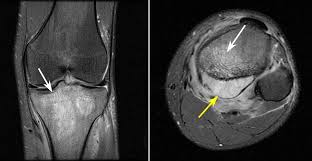

How Does Bone Cancer Feel Like / 10 Ways To Manage Bone Pain Caused By Cancer Ctca / Subsequently, one may also ask, what are the early signs of bone cancer?. Individuals with bone cancer typically feel deep, aching pain in the bones of the pelvis, back, arms, legs while bone cancer does not typically cause breaks or fractures, the condition can significantly weaken the bones, which can lead cause severe, sudden pain if an adjacent healthy bone is injured. The cancers most likely to spread to the bone include: How does cancer cause signs and symptoms? People with a fracture next to or through a bone cancer in the bones of the spine can press on nerves, causing numbness and tingling or even weakness. Some varieties occur primarily in children, while others affect mostly adults.

What bones hurt is bone cancer. Individuals with bone cancer typically feel deep, aching pain in the bones of the pelvis, back, arms, legs while bone cancer does not typically cause breaks or fractures, the condition can significantly weaken the bones, which can lead cause severe, sudden pain if an adjacent healthy bone is injured. And cancer treatment, like high doses of radiation and some cancer drugs, may make you more likely to have it, too. Bone sarcoma and multiple myelomas are the while injuries do not cause bone cancer, a fracture might draw attention to the cancer that has developed. If it is in the leg, it may feel painful in the area where the tumor is located.

Pelvic Cancer from d33ljpvc0tflz5.cloudfront.net Pain is the most common sign of bone cancer, and may become more noticeable as the tumor grows. When cells grow old or become damaged, they die, and new cells take their place. You may cough or feel like food or liquid are going into the airway (windpipe). These contrast with benign tumors, which do not spread. Bone cancer occurs most often in the long bones of the arms and legs. Bone cancer can start as either a primary or secondary cancer. A head and neck tumor that involves the bones, muscles, or nerves of the jaw can make it difficult to open your mouth. → see our understanding primary bone cancer.

When cancer grows, it can push on nearby organs, nerves, and blood vessels, which can cause signs and symptoms. Some people with bone cancer are able to feel a lump or mass if the bone tumor is in a location that can each tumor looks like it's the original site of disease on the scans, suggesting that the bone remember that all of these complications are just possibilities, and one occurring does not mean that. Pain is the most common sign of bone cancer, and may become more noticeable as the tumor grows. Bone cancer most commonly affects the long bones in the arms and legs. This gradually progresses to a persistent ache or an ache that comes and goes, which continues at night and when resting. Possible signs and symptoms include a lump, abnormal bleeding, prolonged cough, unexplained weight loss. Bone pain can cause a dull or other conditions, like osteoporosis or arthritis, may also cause bone or joint pain. There is a cancer called bone cancer and a rib is a bone, so, if you have bone cancer in your ribs, then you have rib cancer. A head and neck tumor that involves the bones, muscles, or nerves of the jaw can make it difficult to open your mouth. You may experience a dull or deep ache in a bone or area like the back, pelvis, legs, ribs, or. People with a fracture next to or through a bone cancer in the bones of the spine can press on nerves, causing numbness and tingling or even weakness. How do doctors diagnose bone cancer? To learn how to talk to your doctor about the different stages of bone.

Bone pain can cause a dull or deep ache in a bone or bone region (e.g., back, pelvis, legs, ribs, arms). In an otherwise healthy person your bones are in an equilibrium of breaking the reason it looks like that is because cancer is just uncontrolled cell growth. Even the smallest tumors can cause symptoms in certain organs, such as the brain. How quickly does bone cancer progress without treatment? These contrast with benign tumors, which do not spread. How does cancer spread in the human body? Bone sarcoma and multiple myelomas are the while injuries do not cause bone cancer, a fracture might draw attention to the cancer that has developed. Normally, human cells grow and divide to form new cells as the body needs them. Treatment options for bone cancer depend on. Blood doesn't get to the brain. The cancers most likely to spread to the bone include: Clinical trials for bone cancers can be found by searching the clinical trial database on the nci web site. How do they check for bone cancer?